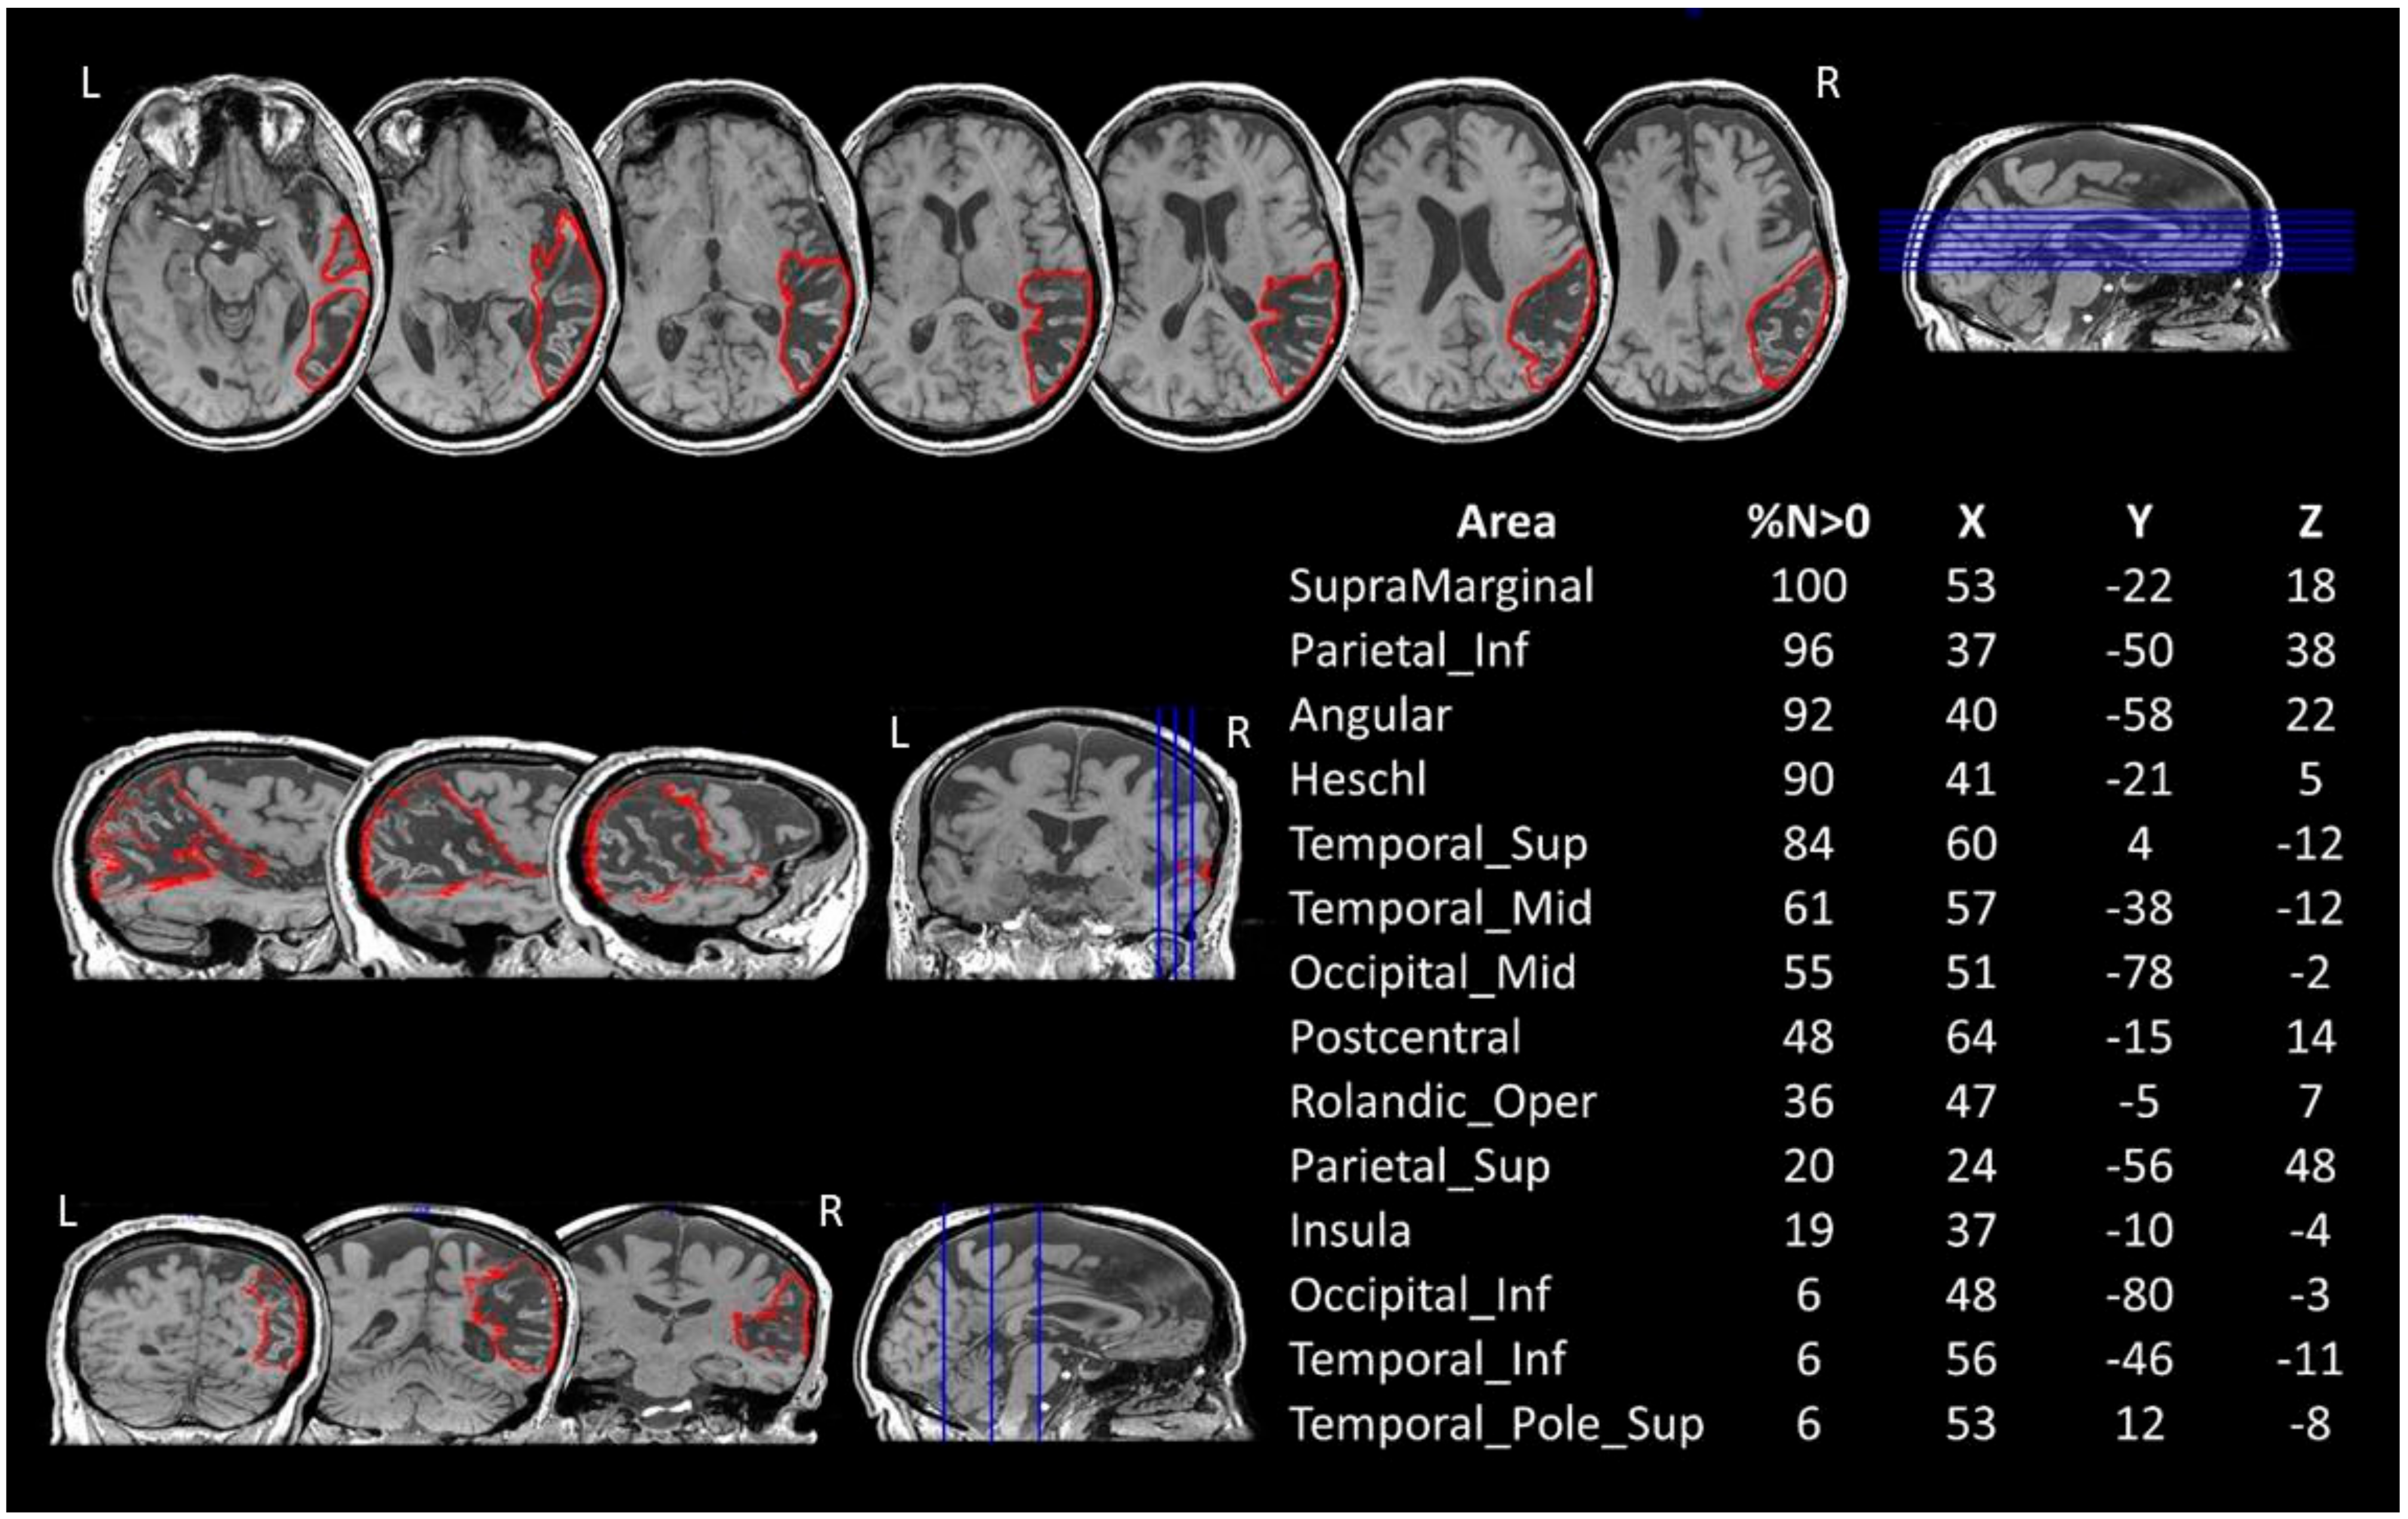

Figure 1.

BG’s 3D-T1 MRI image and lesion mapping. Axial (up), sagittal (middle-left) and coronal (bottom-left) views are shown with the drawing of the lesion in the right hemisphere in red. The table on the right reports the percentage volume (%N > 0) affected by the lesion and the MNI coordinates (X, Y, Z) for each grey matter structure, as reported on MRIcron (AAL atlas). Lesion’s centre of mass = 140.42 × 84.64 × 97.34. L = left. R = right.

The comparison between AP’s lesions and the AAL template is shown in Figure 1.

The patient’s lesion in the right hemisphere extends out from pericentral regions, the insula and the temporal lobe to the inferior parietal and occipital cortices. No direct damage to the frontal cortex was recorded.